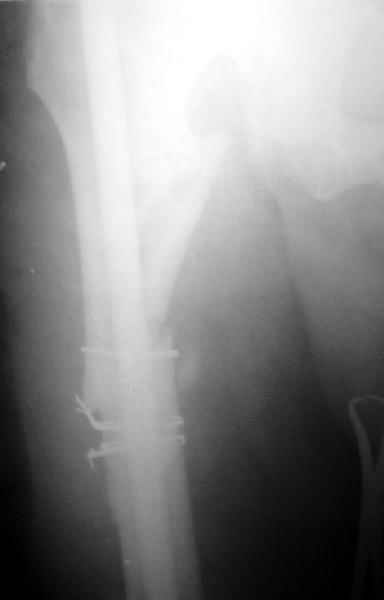

В районной больнице больному выполнен остеосинтез обоих бедер штифтом Кюнчера и накостный остеосинтез правой плечевой кости. Через год больной поступил к нам с ложным суставом шейки левого бедра, обеих бедер и правой б/б кости. Нами выполнено остеосинтез правой голени и левого бедра пластиной Абдуразакова (угольникообразная пластина) с аутокостной пластикой (трансплантат 1/3 ширины малоберцовой кости, длиной 12-14 см.). Через 6 месяцев в связи жалоб больного на хруст, боль и не возможность сидеть, больному произведено цервикокапитальное эндопротезирование головки левого бедра. Больной не посоветовавшись с нами, активно стал разрабатывать левый коленный сустав, в результате через 3 месяца после последней операции поступил с изломом пластины (рис.1). На наш взгляд, оптимальным решением было выполнение остеосинтеза блокирующими гвоздями обеих бедер (рис2). Это первые операции с использованием подобных гвоздей (получили по гум.помощи), поэтому практики по использованию их у нас нет.1. используются ли эти гвозди при ложных суставах?2. Больной в течение этих лет не ходит, можно ли его ставить на ноги?3. Как вести дальше этого больного?4. Какие возможно были варианты остеосинтеза, кроме реэндопротезирования ревизионной ножкой?Заранее благодарю, Алишер.